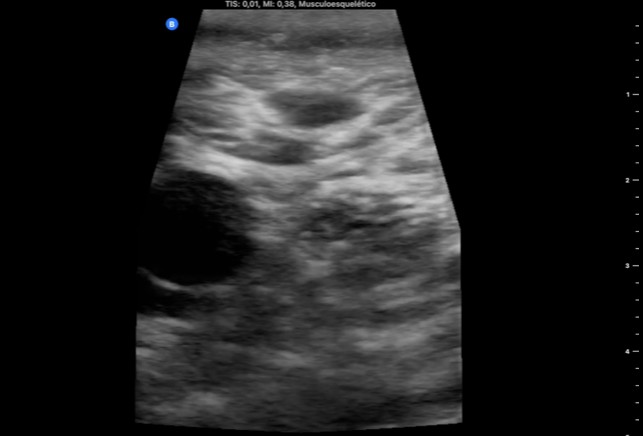

Se realiza ecografía.

En el caso 1, en la ecografía de control se objetiva trombo a casi 1 cm del cayado safeno-femoral. En el caso 2 se realiza ecografía con ecógrafo portátil y se objetiva trombosis venosa superficial en venas infrapoplíteas de MID.